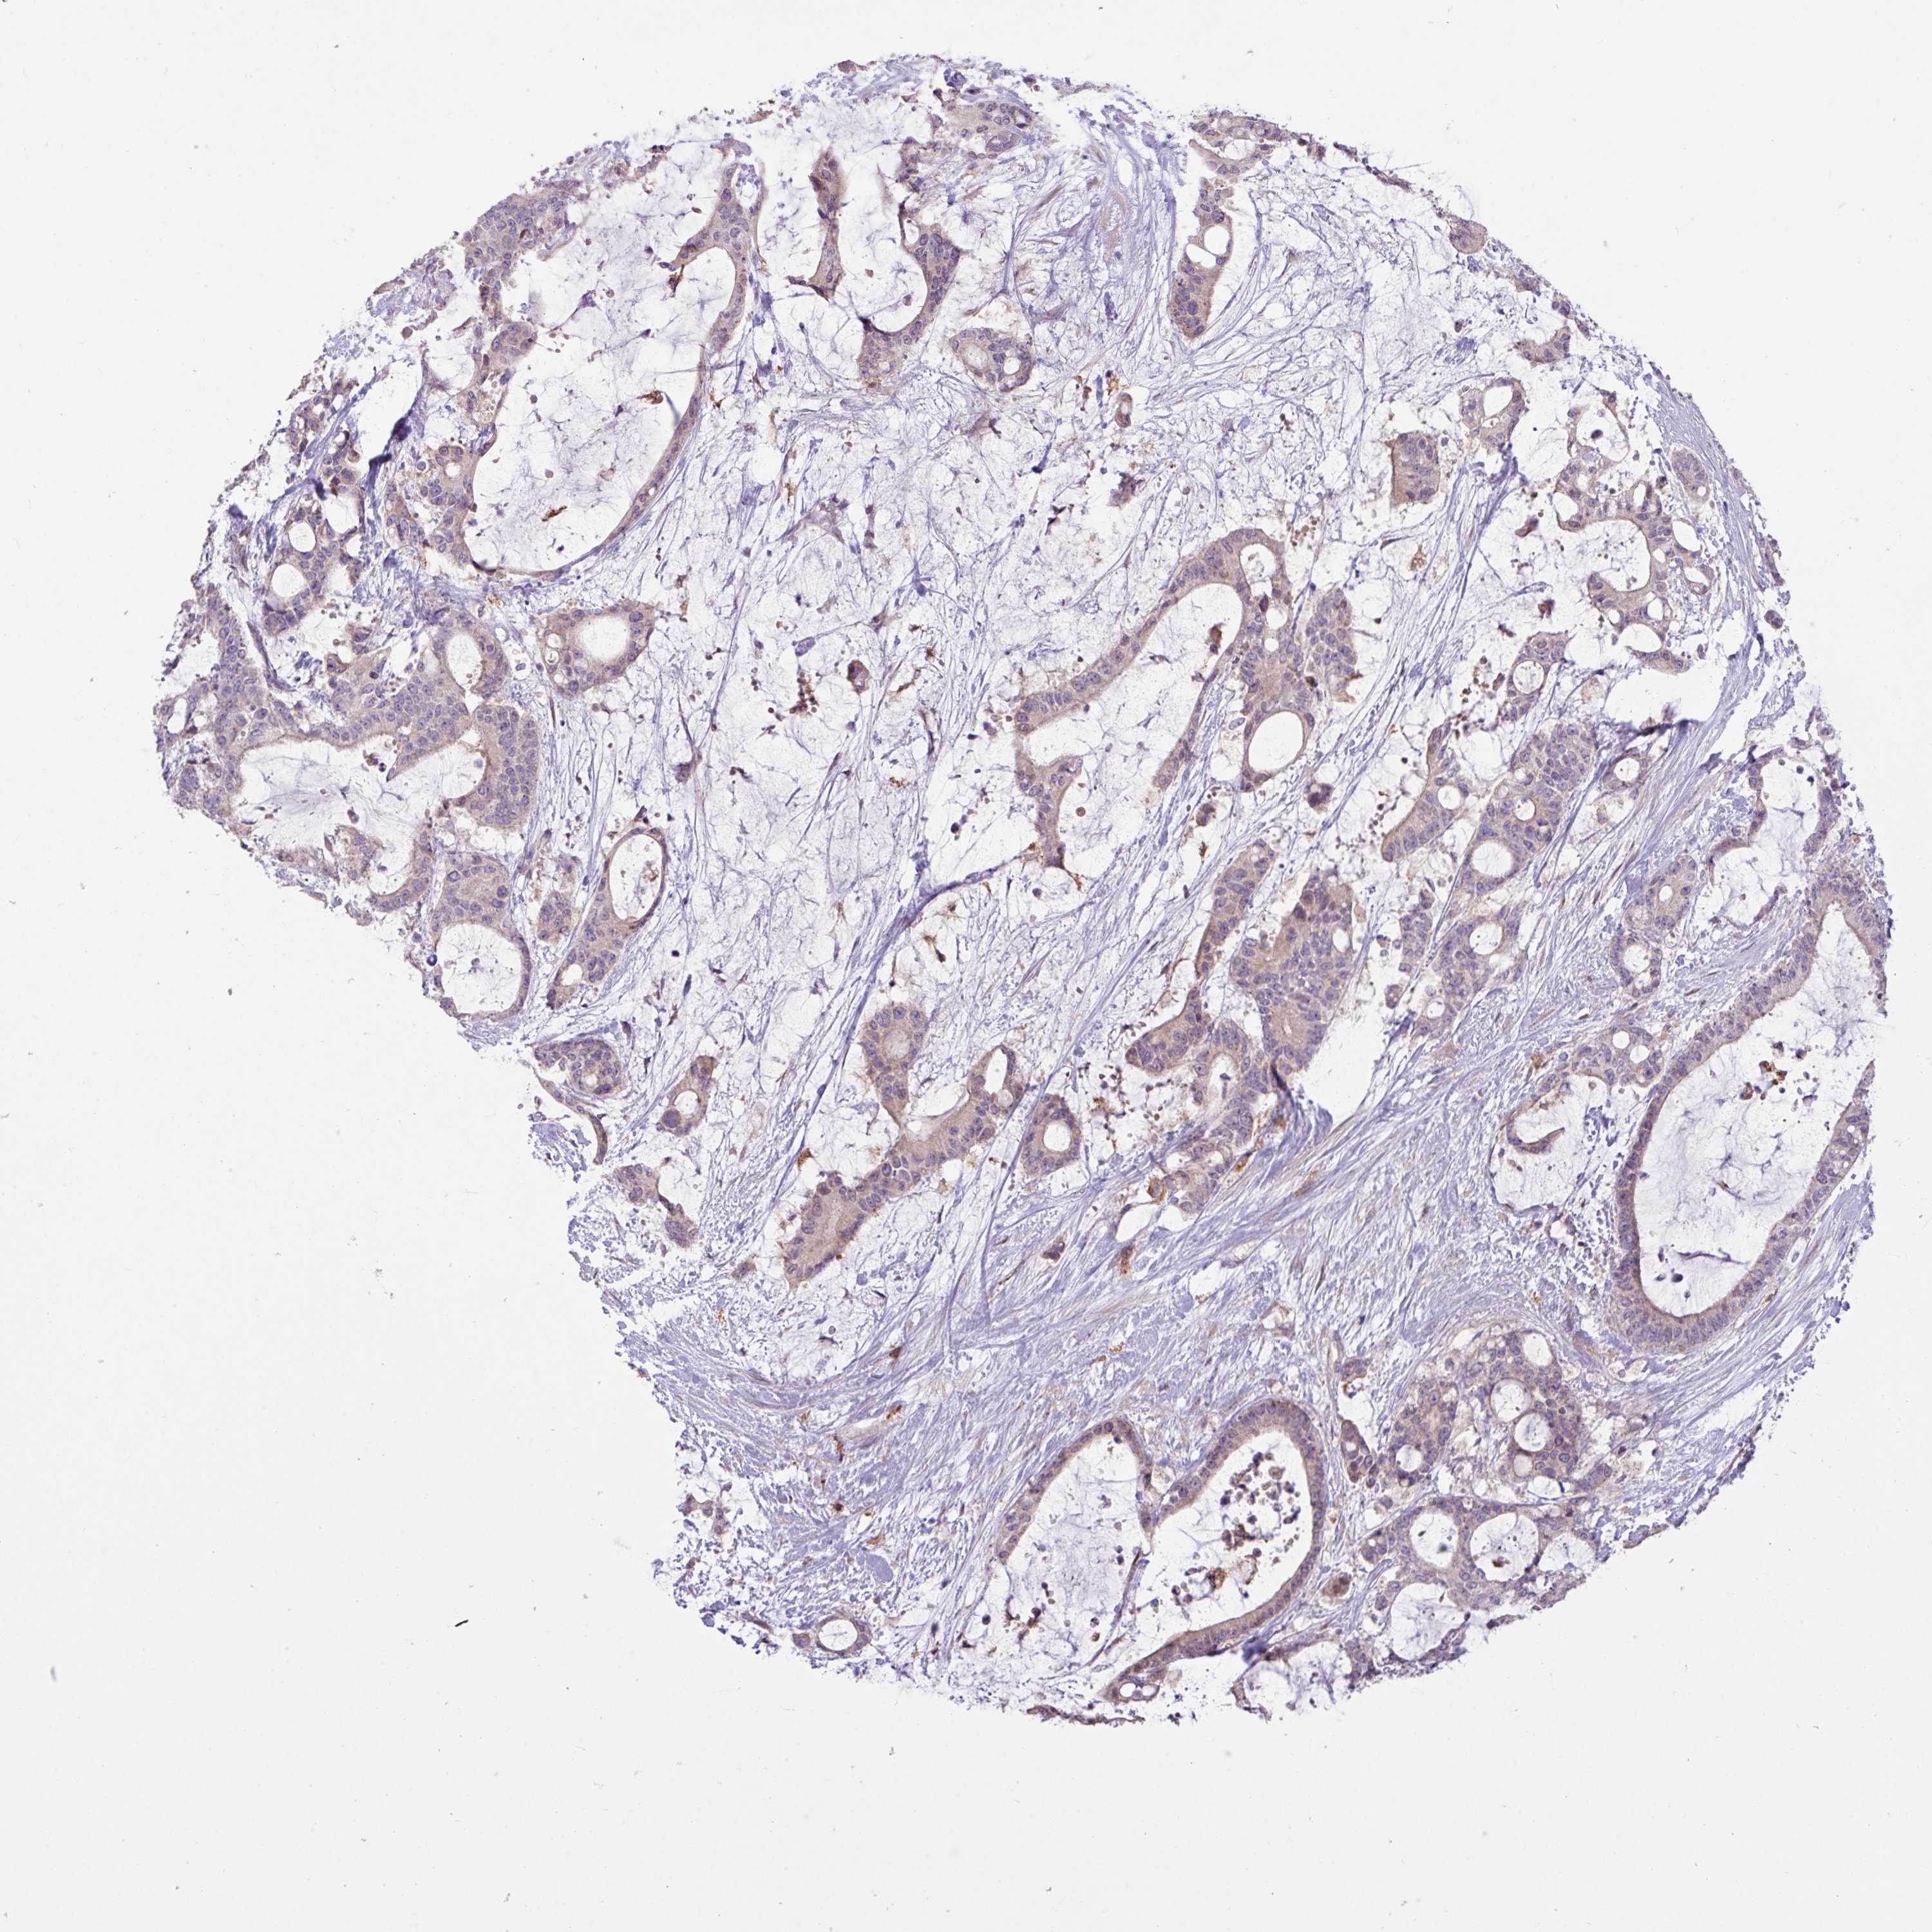

LIVER CANCER - Protein expressioni

A mouse-over function shows sample information and annotation data. Click on an image to view it in a full screen mode. Samples can be filtered based on level of antibody staining by selecting one or several of the following categories: high, medium, low and not detected. The assay and annotation is described here.

Note that samples used for immunohistochemistry by the Human Protein Atlas do not correspond to samples in the TCGA dataset.

Antibody stainingi

Antibody staining in the annotated cell types in the current human tissue is reported as not detected, low, medium, or high, based on conventional immunohistochemistry profiling in selected tissues. This score is based on the combination of the staining intensity and fraction of stained cells.

Each image is clickable and will lead to virtual microscopy that enables deeper exploration of all samples and also displays staining intensity scores, fraction scores and subcellular localization as well as patient and tissue information for each sample.

Antibody HPA052016

Staining

High

Medium

Low

Not detected

Intensity

Strong

Moderate

Weak

Negative

Quantity

>75%

75%-25%

<25%

None

Location

Nuclear

Cytoplasmic/membranous

Cytoplasmic/membranous,nuclear

Carcinoma, Hepatocellular, NOS

Cholangiocarcinoma